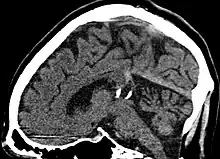

Pineal gland cyst

Calcified cyst of pineal gland in CT. Sagittal MPR.